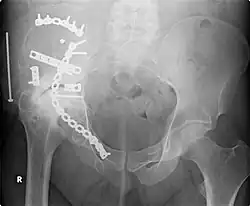

Orthopedic surgery or orthopedics (alternative spelling orthopaedics) is the branch of surgery concerned with conditions involving the musculoskeletal system.[1] Orthopedic surgeons use both surgical and nonsurgical means to treat musculoskeletal trauma, spine diseases, sports injuries, degenerative diseases, infections, tumors and congenital disorders.

External fixation of fractures was refined by American surgeons during the Vietnam War, but a major contribution was made by Gavril Abramovich Ilizarov in the USSR. He was sent, without much orthopedic training, to look after injured Russian soldiers in Siberia in the 1950s. With no equipment, he was confronted with crippling conditions of unhealed, infected, and misaligned fractures. With the help of the local bicycle shop, he devised ring external fixators tensioned like the spokes of a bicycle. With this equipment, he achieved healing, realignment, and lengthening to a degree unheard of elsewhere. His Ilizarov apparatus is still used today as one of the distraction osteogenesis methods.[12]

- Orthopedic trauma

- Repair of femoral neck fracture

- Repair of trochanteric fracture

- Repair of femoral shaft fracture